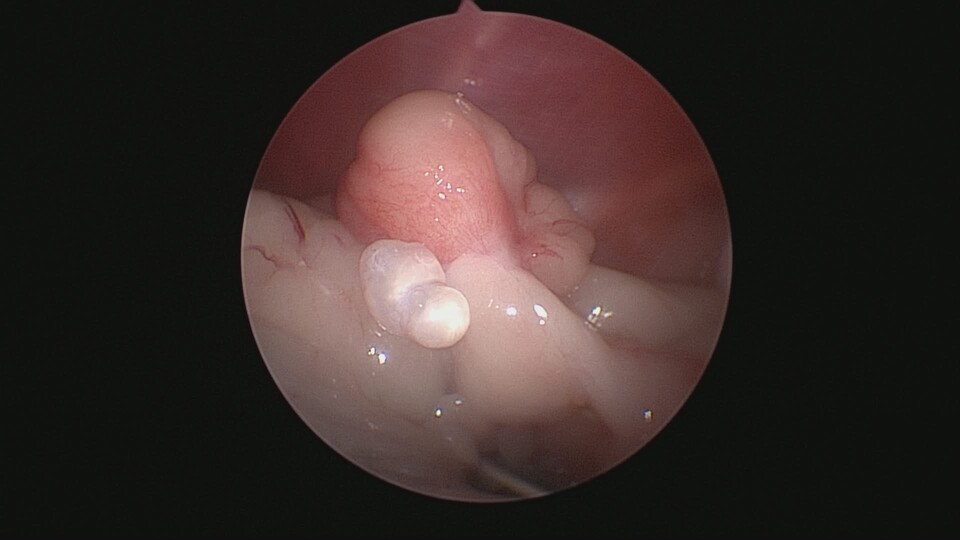

卵巢殘留症候群是指在進行卵巢子宮切除術(OHE)後,卻因卵巢組織未完全切除,導致體內仍有部分卵巢組織殘留,進而分泌性激素,引發類似發情的症狀。常見於狗與貓,可能會出現陰道分泌物、行為改變、乳腺腫脹等現象。

*卵巢組織切除不完全

*解剖位置異常導致遺漏

*手術視野不佳或操作困難

*腹腔沾黏使卵巢不易辨認